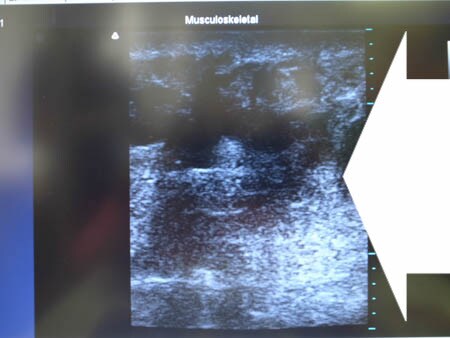

いつものように3Dタッチビュー(超音波)で

皮下脂肪層を評価してみましょう。

右二の腕

↓ ↓ ↓

上の画像の部分の皮下脂肪層をつまんでみましょう。